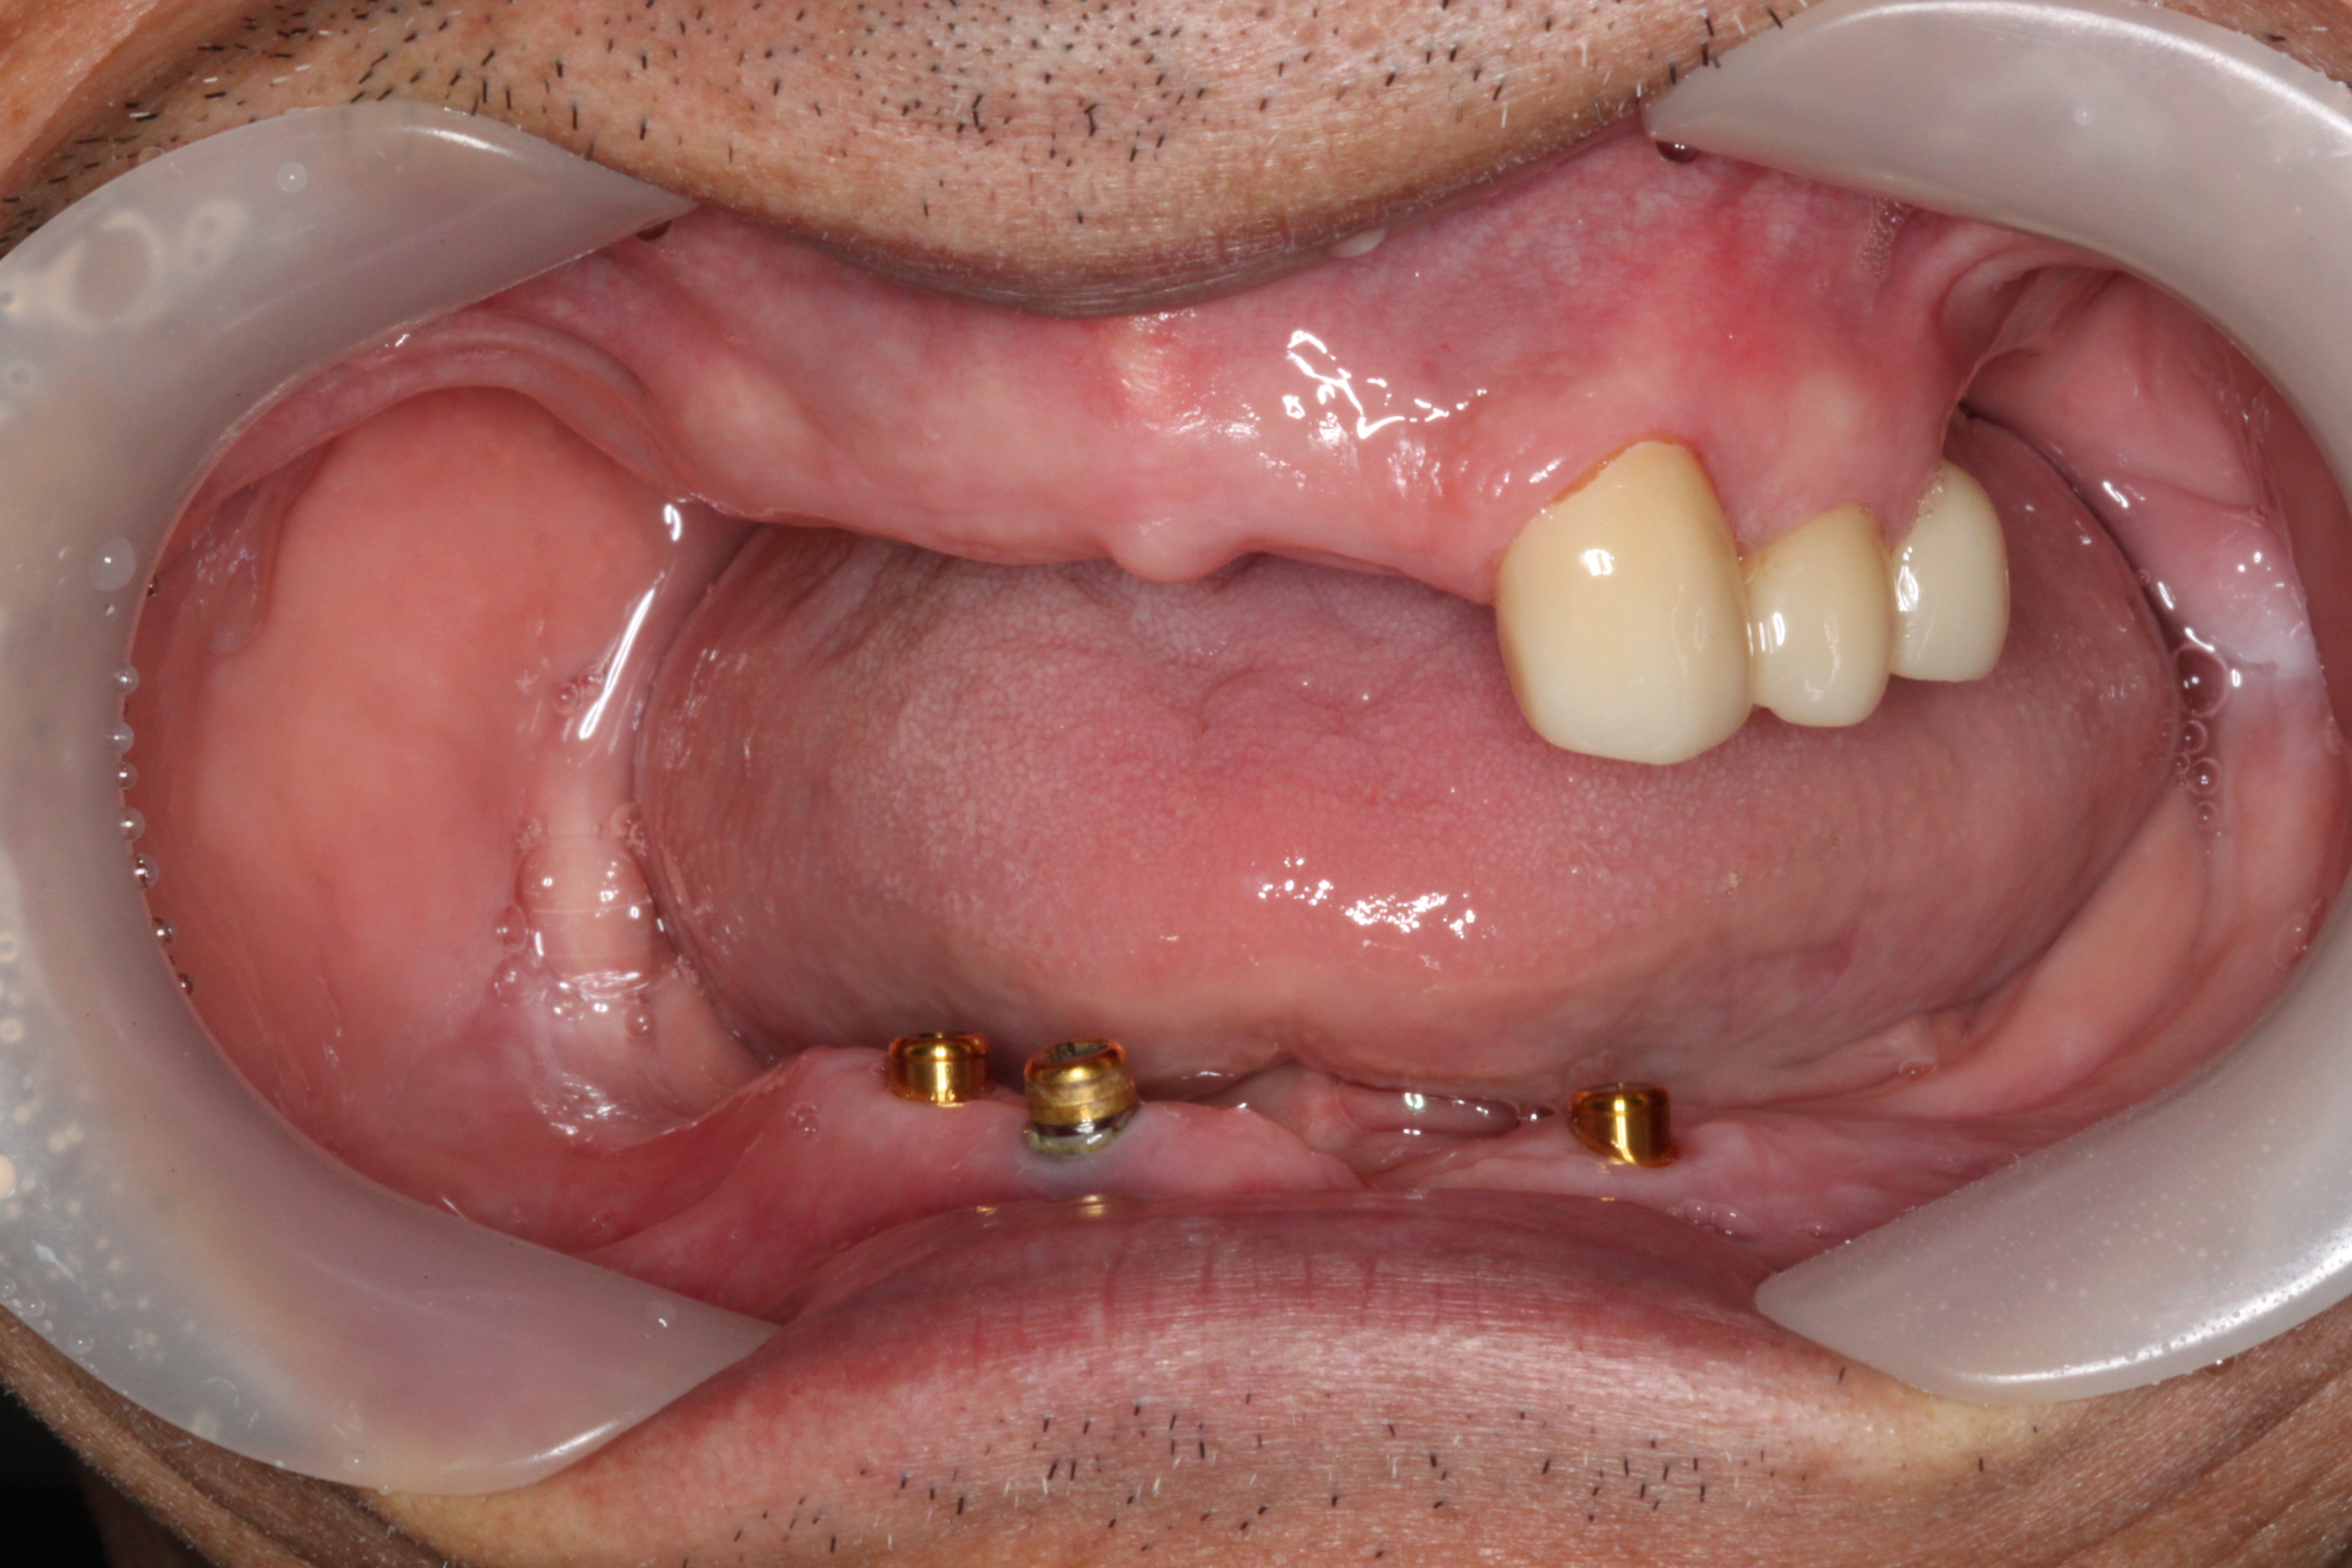

BEFOREAFTERBEFOREAFTER(식립)AFTER(착용)